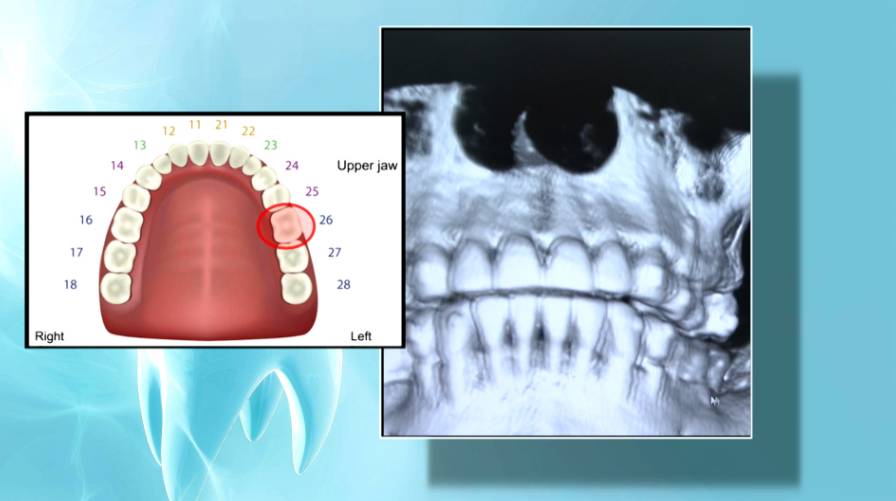

這宗醫療事故始於2020年,葉女士在觀塘一間診所由陳醫生為她拔除上顎大牙。手術後,她便時常感到拔牙位置疼痛、鼻塞及呼吸不順。情況持續了整整三年,直到2023年8月,她因打算在內地植牙而照X光,才驚恐地發現,導致她長期不適的元兇,正是一截被遺留在牙槽骨內的牙腳。她隨即回到涉事診所對質,但陳醫生卻一直「請病假」,診所最終僅轉介她到另一位醫生處進行手術移除牙腳。

專家揭疼痛根源 鼻竇炎或因殘留牙腳

為查明真相,《東張西望》陪同葉女士尋求牙科專家陳澔賢醫生的協助。經過詳細檢查,陳醫生明確指出,葉女士的鼻竇炎問題,極有可能是由當年剝牙時殘留的牙腳所引起。這個專業判斷,總算為葉女士長年承受的痛苦找到了一個科學解釋,證實了她的身體不適並非無的放矢,而是源於該次醫療失誤的直接後果。